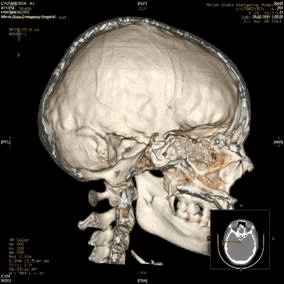

Краниологическое исследование пациентов проводилось в УЗ «Больница скорой медицинской помощи» г. Минска (Республика Беларусь) с помощью 16-срезового компьютерного томографа «General Electric LightSpeed Pro 16» и его программного обеспечения. В базе данных компьютерного томографа пациентов можно сортировать по возрасту, полу, области исследования, дате исследования и др. Сканирование пациентов осуществлялось в положении головы во франкфуртской горизонтальной (ухоглазничной) плоскости, которая проходит между наиболее низкой точкой глазницы и наиболее высокой точкой на верхнем крае наружного слухового прохода. Результат исследования выводится на экран в двухмерной сагиттальной и горизонтальной плоскостях (рис. 1 слева). Костные структуры выглядят светлыми, мягкие ткани — темными с разной степенью интенсивности цвета. Программное обеспечение томографа также позволяет произвести реконструкцию и построить трехмерное изображение черепа (рис. 1 справа).

Рис. 1. Режимы изображения в сагиттальной плоскости (двухмерный 2D — слева и трехмерный 3D — справа)

С помощью трехмерной реконструкции исследователю предоставляется возможным качественно оценить строение черепа, его костные образования, толщину кости. Трехмерные модели можно вращать, изменять их масштаб, производить срезы на необходимом уровне и др. В данном режиме также возможно производить измерения краниометрических параметров, однако их точность ниже, чем при измерении в режиме 2D-изображения.